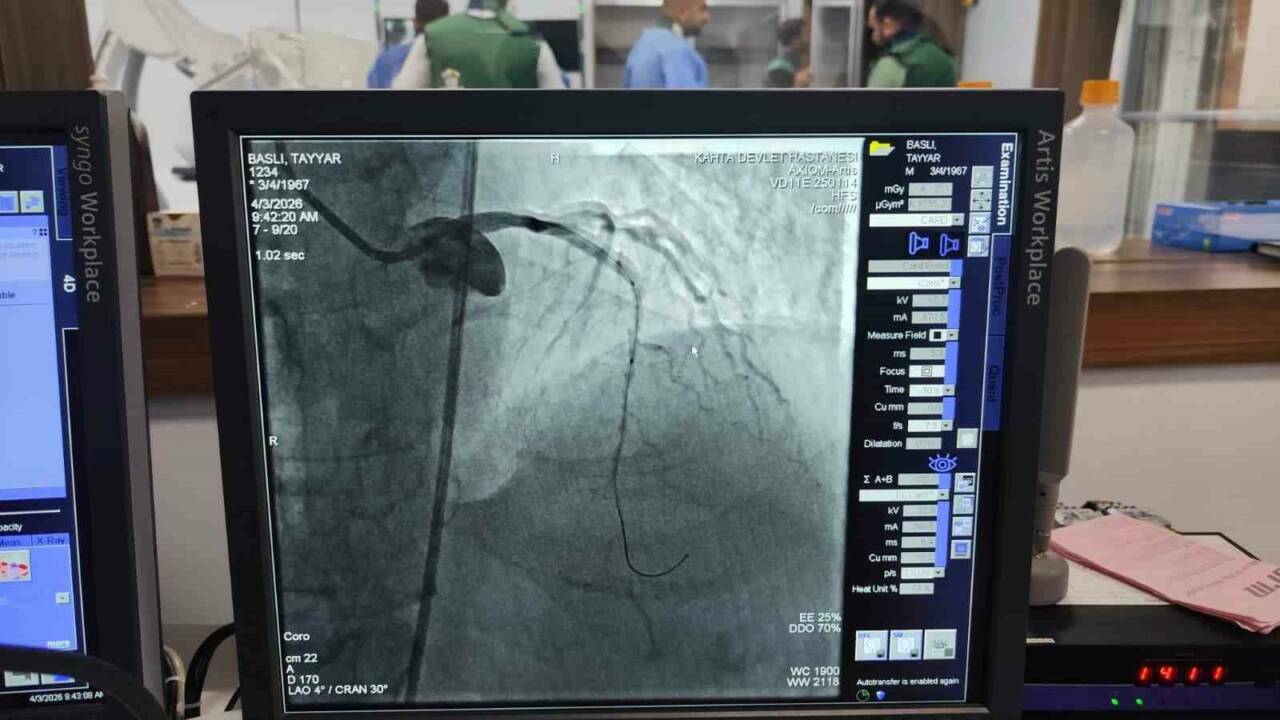

Kâhta Devlet Hastanesi Başhekimi Dr. Mustafa Akel, “Hastanemizden 45 km mesafede ikamet eden 59 yaşındaki hastamız, göğüs ağrısı şikâyeti ile hastanemize başvurmuştur. Yapılan tetkiklerde kalp krizi geçirdiği tespit edildi ve acil bir şekilde yeni açmış olduğumuz anjio merkezimize hastayı aldık. Yapılan görüntülemede kalbinin ön damarı olan LAD mid bölgesi total tıkalı tespit edildi. Hastamızın kalbinin ön damarına iki adet stent takarak tam açıklık sağlandı. Hastamızın genel durumu iyi olup yoğun bakıma takip amacıyla alındı” dedi.